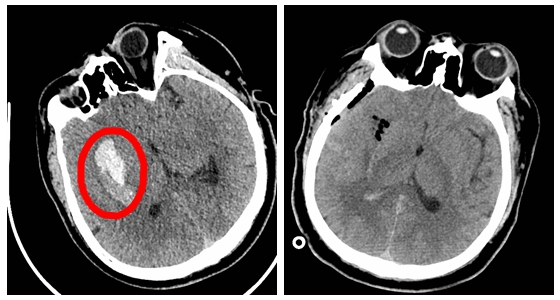

手术前后对比图

1月23日15:03,刘景平教授手术团队为患者施行了“颅内血肿清除术”。术中暴露脑组织后分开侧裂血管,仅开放1公分左右的瘘口将脑深部血肿全部清除。手术顺利,术后患者生命体征平稳,带气管插管送入重症监护室进一步监护治疗。